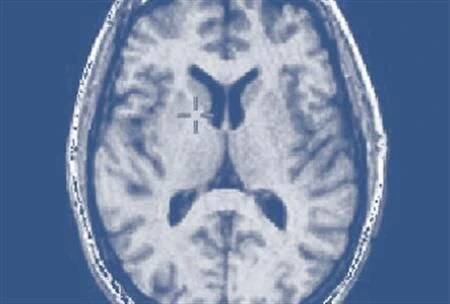

MRI mozku: show mozku nádor v pravém mozkovém laloku mozku